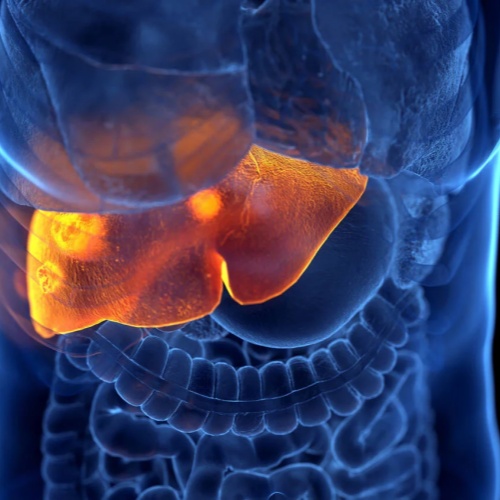

三、ECT在肝癌中的应用

Liver cancer(包括原发性和转移性肝肿瘤)的治疗通常较为复杂,涉及手术、放疗、化疗及局部消融等多种手段。

近年来,一些医疗中心开始尝试将ECT应用于肝癌治疗。来自Universitätsklinikum Regensburg的专家指出,ECT可以在保护周围正常肝组织的同时,实现有效的肿瘤消融。

这一特点对于肝脏这样“功能关键且再生能力有限”的器官尤为重要。